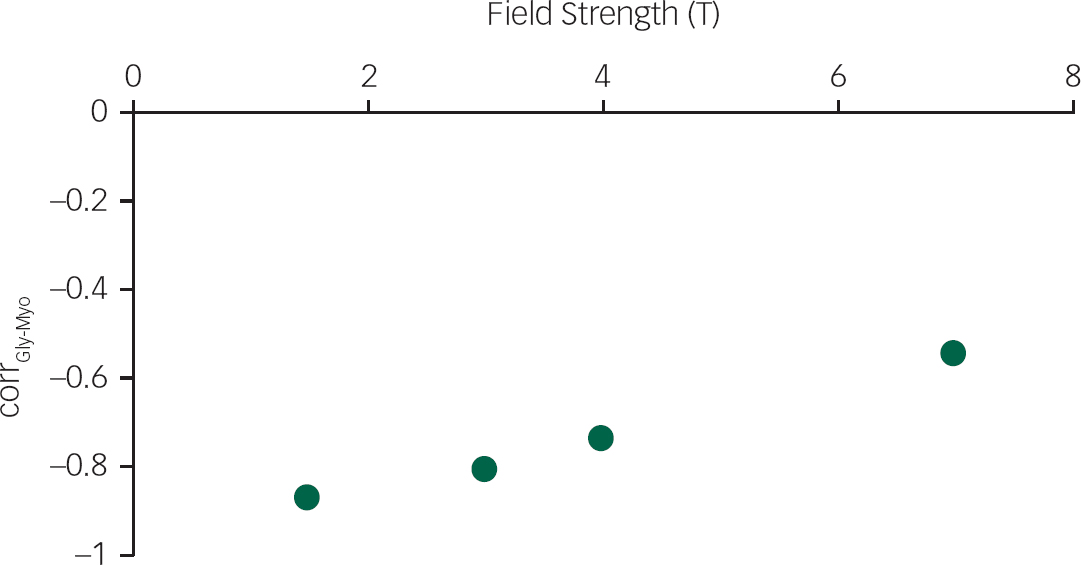

To demonstrate the feasibility of quantifying Gly separately from Myo at 7 T, 500 simulations of Gly and Myo spectral signatures with known concentrations for the same STEAM sequence (TE=10 ms, TM=32 ms) at each of the 4 B0 (1.5 T, 3 T, 4 T and 7 T) were created and given random noise comparable to a 64 average spectrum, and then fit. The amount of noise was determined using the SNR value for a single 7 T scanReference Mangia, Tkác, Gruetter, Van de Moortele, Maraviglia and Uğurbil 34 and assuming a linear SNR change with B0. Correlations between Gly and Myo concentrations were then calculated.

The simulations of Gly and Myo demonstrated significantly improved separation of the two metabolites at 7 T compared to 1.5 T (P<0.001), 3 T (P<0.001) and 4 T (P<0.001) (Fig. 2). In vivo 1H-MRS spectra were acquired with voxels in the ACC and thalamus of all participants with the exception of one healthy control who did not wish to finish the scan of the thalamus because of dizziness. Average water linewidths were 13.2 (1.3) Hz and 16.9 (2.1) Hz for the healthy controls, 12.1 (0.9) Hz and 16.0 (1.8) Hz for the MDD group, and 12.8 (1.6) Hz and 16.9 (2.2) Hz for the schizophrenia group in the ACC and thalamus, respectively, indicating well shimmed data. There were no significant differences in the water linewidths between groups, and there were no significant differences in grey matter, white matter or cerebrospinal fluid volume per voxel between groups. One spectrum from the ACC of volunteers from each of the MDD and schizophrenia groups needed to be excluded because of poor-quality spectra, likely because of excessive movement. Example spectra from each brain region with spectral fits of Glu, Gln, Gly and the macromolecular spectrum can be seen in Fig. 1. In the thalamus, one patient from the schizophrenia group and one healthy control each presented with Gly concentrations that had CRLB of 35% and were excluded.

Fig. 2 The correlation between glycine and myo-inositol concentration estimates (corrGly-Myo) for 500 noisy realisations of a STEAM sequence (TE=10 ms, TM=32 ms) containing only glycine and myo-inositol spectral signatures, at four field strengths (1.5 T, 3 T, 4 T and 7 T), with a signal-to-noise ratio comparable to 64 averages at each field strength.